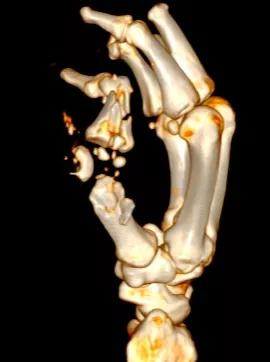

三维CT显示粉碎骨折的右手拇指